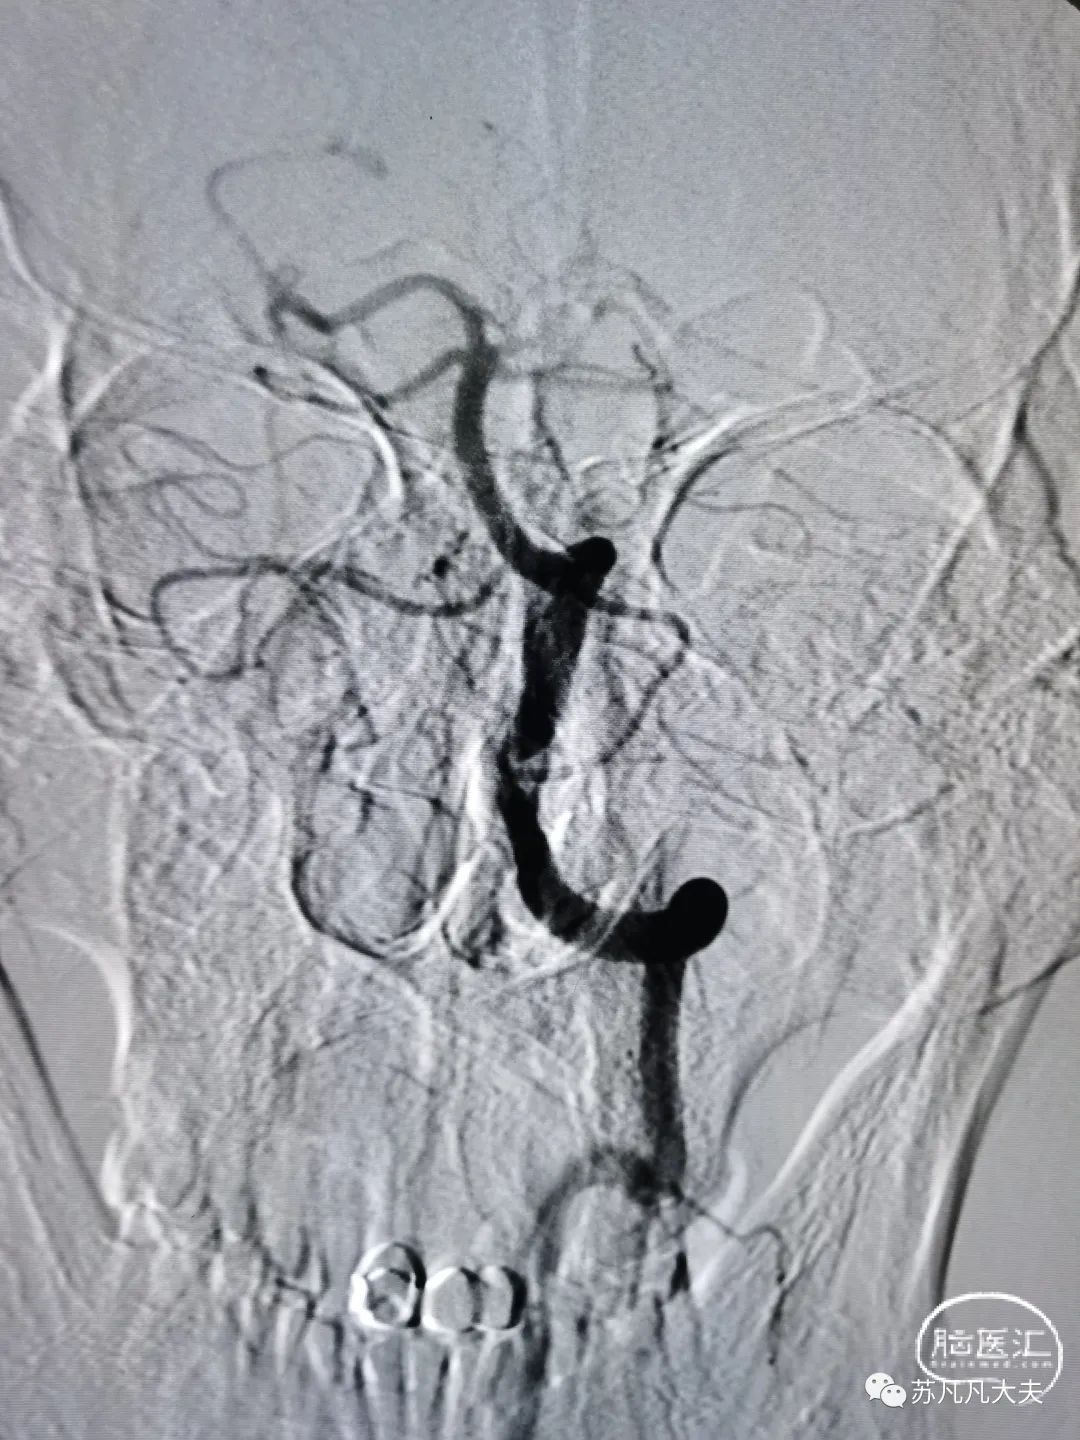

DSA示左椎优势,V4段极重度狭窄,左侧大脑后动脉未显影

脑血管造影提示

患者右椎发育不良,左椎优势,颅内段极重度狭窄,狭窄远端存在双侧小脑后下动脉,导致低灌注,同时左侧大脑后动脉未显影,考虑系狭窄基础上血栓形成后脱落致大脑后动脉栓塞。